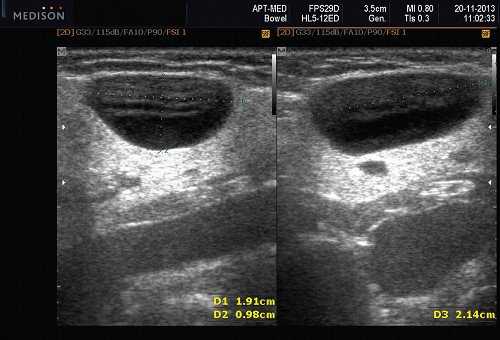

Общие особенности при ультразвуковом исследовании. Лучший диагностический признак: четко очерченная внутрижелезистая опухоль ПЧЖ, которая может выступать на ножке от края железы в поднижнечелюстное пространство (ПЧП), когда она становиться большой

Морфология. Малая плеоморфная аденома: одиночная, цельная, яйцевидная и хорошо разграниченная опухоль. Большая плеоморфная аденома на УЗИ: дольки ± кровоизлияние или некроз ± кальцификация

Результаты ультразвукового исследования слюнной железы

Серошкальное УЗИ. Хорошо выраженная, солидная и гипоэхогенная по сравнению с прилегающей тканью слюны. Однородная внутренняя эхо-структура с задним акустическим усилением. Опухоль имеет несколько тканевых границ и позволяет звуку легко проникать, вызывая улучшение заднего отдела. Большие опухоли могут иметь неоднородные внутренние эхосигналы из-за кровоизлияния и некроза. Гетерогенная плеоморфная аденома может иметь нечеткие границы, имитирующие злокачественную опухоль. Большие опухоли могут иметь дольки и появляться на ножке. Необычный кальциноз при ультразвуковом сканировании наблюдается при давней опухоли. Кожа и подкожные ткани в норме